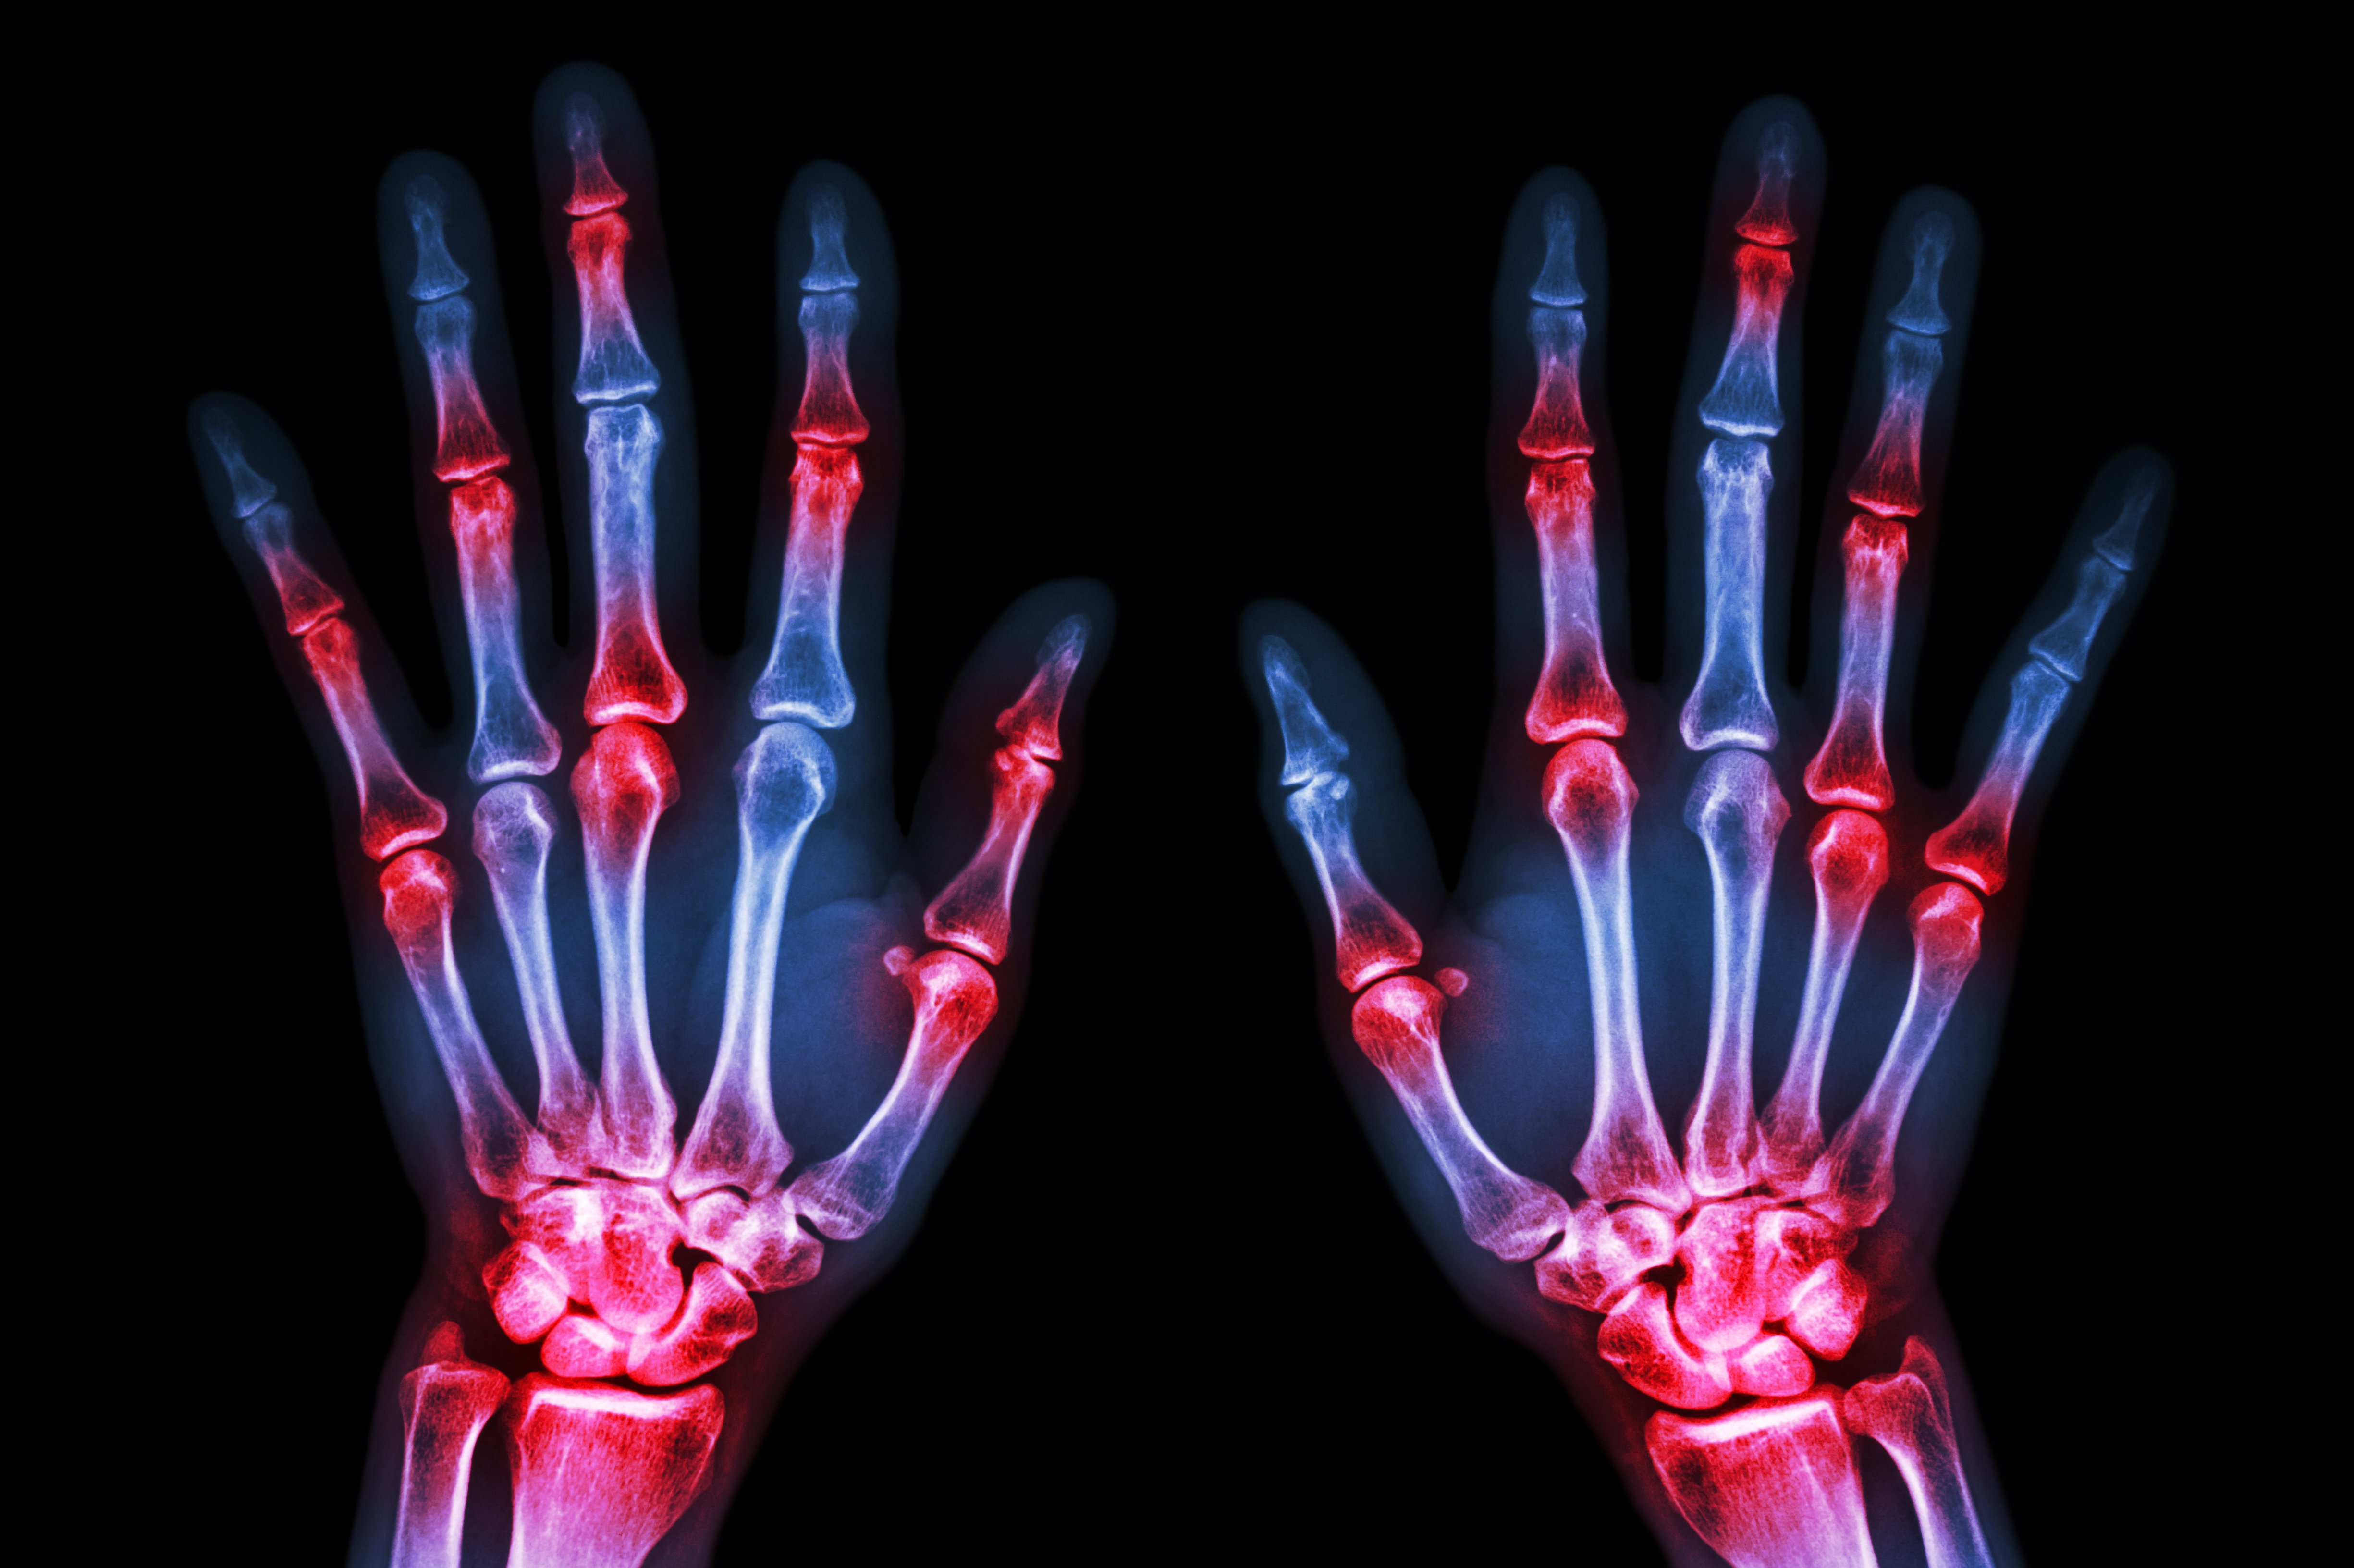

(Vienna, 21 February 2020) Two indices for assessing disease activity in rheumatoid arthritis that have been developed at MedUni Vienna are increasingly regarded as the gold standard in clinical practice and in scientific applications. The "Simplified Disease Activity Index" and the "Clinical Disease Activity Index" record changes, allow a clear distinction between low, moderate and high disease activity, include remission criteria and are simple to use in everyday clinical practice. Most of the revenue generated from copyright royalties is ploughed straight back into rheumatology research at MedUni Vienna.

Daniel Aletaha and Josef Smolen from the Division of Rheumatology of the Department of Medicine III of MedUni Vienna/Vienna General Hospital have been collaborating for years on the research and development of better and simpler instruments for assessing disease activity in rheumatoid arthritis. They developed the "Simplified Disease Activity Index" (SDAI), which is based on the examination of 28 joints, an assessment of disease activity by patient and doctor and measurement of the CRP level. If one were to omit the CRP laboratory value, one then has the even simpler "Clinical Disease Activity Index" (CDAI).

The SDAI and the CDAI reflect disease activity very effectively, record changes, allow a clear distinction to be made between low, moderate and high disease activity, include remission criteria and are easy to use in everyday clinical practice.